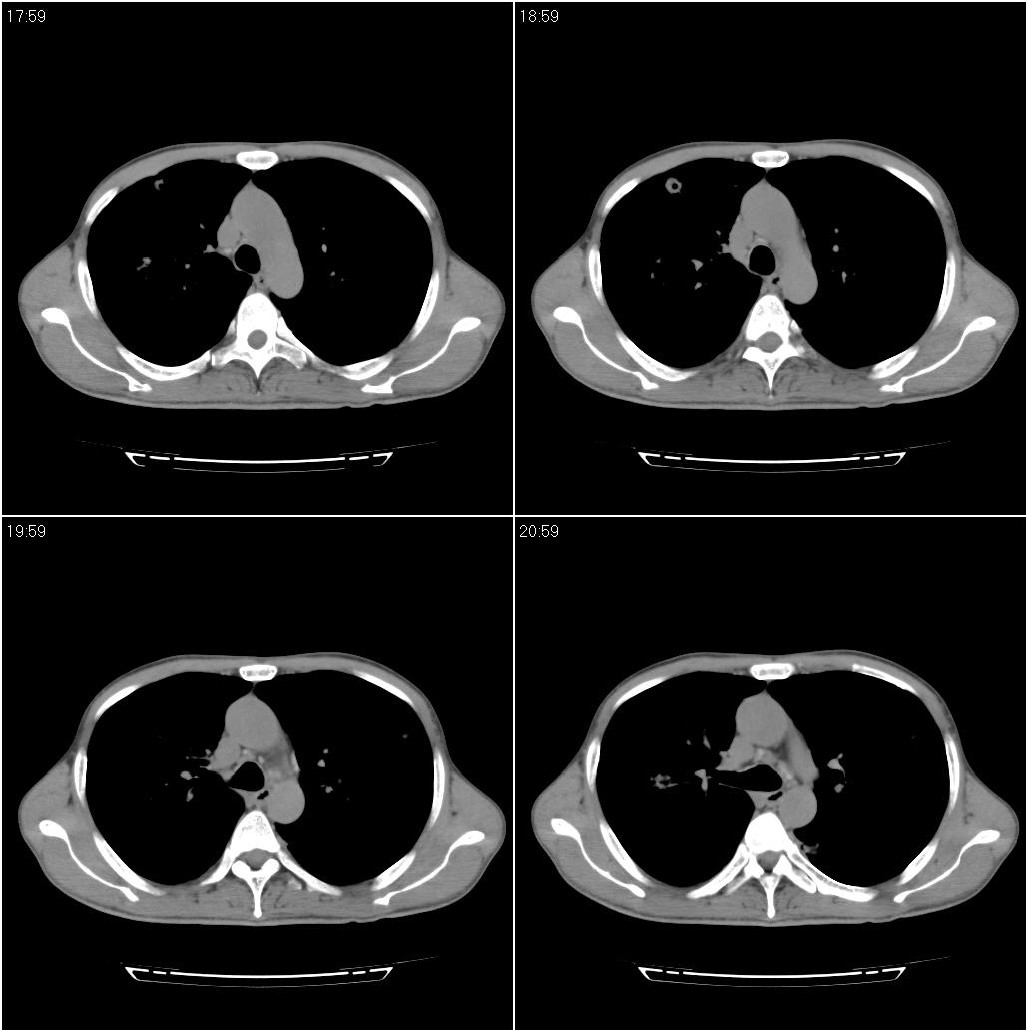

两肺继发性肺结核并多发性结核球形成,部分病灶内空洞形成。

两肺继发性肺结核并多发性结核球形成,部分病灶内空洞形成

两肺继发性肺结核并多发性结核球形成,部分病灶内空洞形成。支持